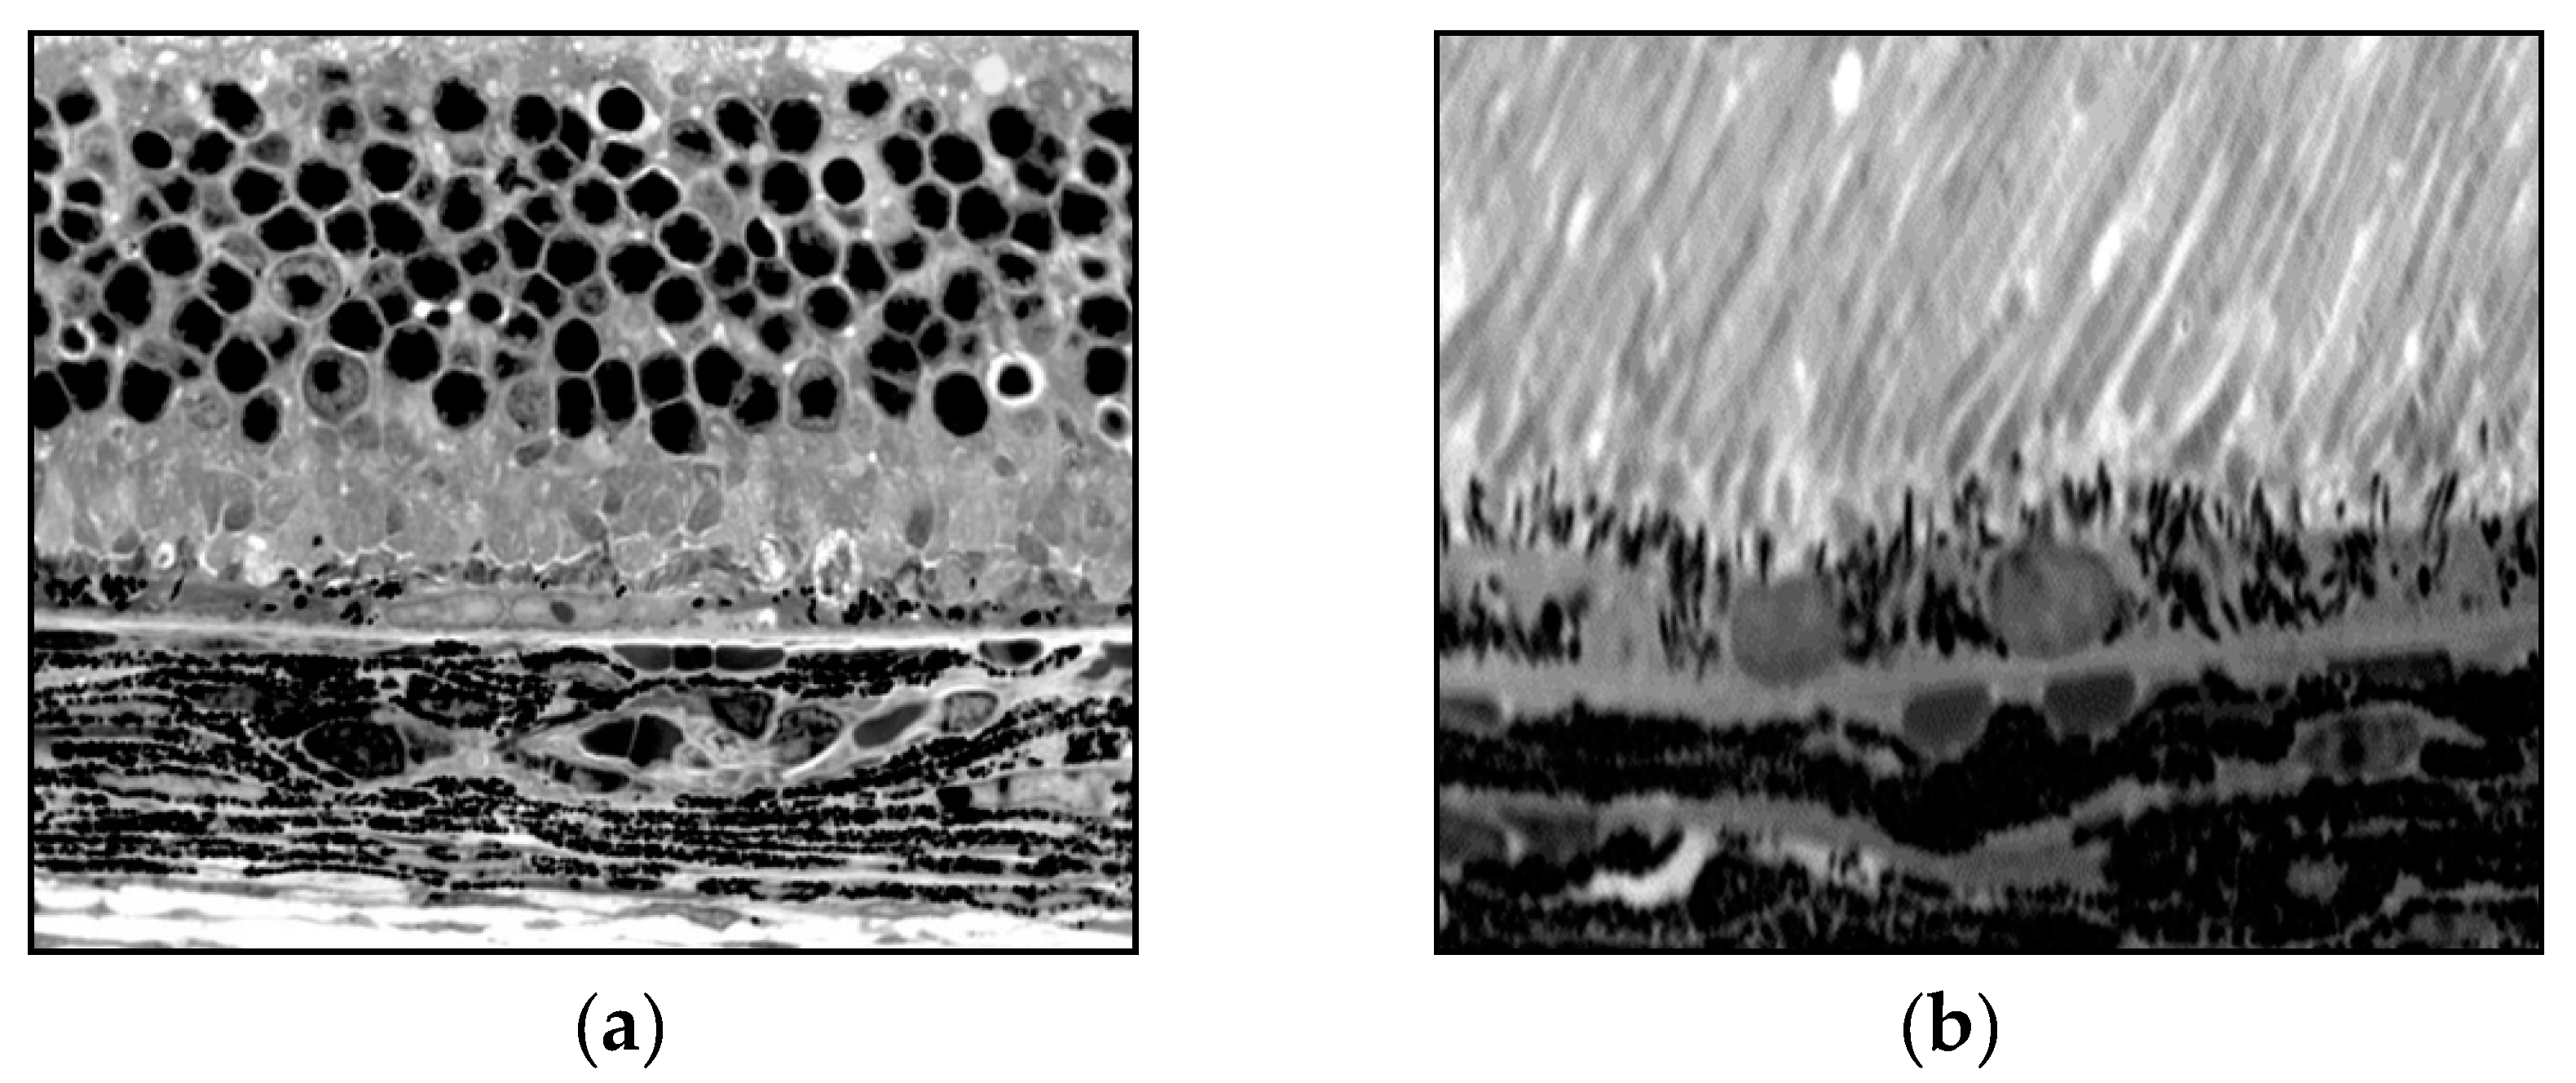

Histological Studies

Retinal changes after 1-mg PEG injection

Dry AMD like changes after 0.5-mg PEG injection